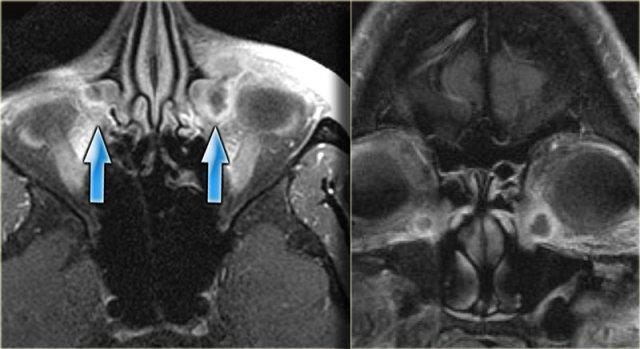

Một biến chứng hiếm gặp của phẫu thuật nội soi xoang chức năng (FESS) được thấy trong các hình ảnh bên trái.

Đơn vị Hounsfield của các bất thường nhỏ mà dấu hoa thị chỉ vào vào khoảng -120.

Trước tiên hãy quan sát các hình ảnh mặt phẳng axial.

Sau đó tiếp tục với các hình ảnh mặt phẳng coronal.

Có khuyết xương tại trần sàng (fovea ethmoidalis) (mũi tên đỏ).

Ngoài ra còn có các thay đổi sau phẫu thuật cho thấy bệnh nhân đã trải qua phẫu thuật FESS.

Khí nội sọ là biến chứng của phẫu thuật FESS.

Với biến chứng này, thông thường bệnh nhân ra về trong tình trạng ổn định, sau đó tái nhập viện khoảng hai tuần sau với tình trạng rò dịch não tủy và viêm màng não, do khuyết xương và màng cứng.

Tràn khí nội sọ áp lực xảy ra khi khí trong hộp sọ hoạt động như một khối choán chỗ: có khuyết xương cho phép khí đi vào nhưng không thoát ra được (chức năng như van một chiều).

Mỗi lần bệnh nhân hắt hơi, khí bị đẩy qua chỗ khuyết vào khoang nội sọ và bị giữ lại ở đó.

Đến một thời điểm nhất định, lượng khí đủ lớn để gây hiệu ứng khối lên các cấu trúc nội sọ xung quanh.